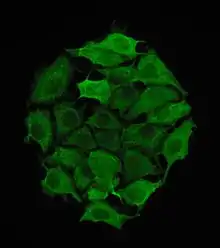

Keratin, type II cytoskeletal 8 also known as cytokeratin-8 (CK-8) or keratin-8 (K8) is a keratin protein that is encoded in humans by the KRT8 gene. It is often paired with keratin 18.

Utility as an immunohistochemical stain

Antibodies to CK8 (e.g. CAM 5.2) can be used to differentiate lobular carcinoma of the breast from ductal carcinoma of the breast.[5] CAM 5.2, an antibody that reacts with an epitope found on both CK8 and CK18, is used in immunohistochemistry to demonstrate certain forms of cancer. In normal tissue, it reacts mainly with secretory epithelia, but not with squamous epithelium, such as that found in the skin, cervix, and esophagus. However, it also reacts with a range of malignant cells, including those derived from secretory epithelia, but also some squamous carcinomata, such as spindle cell carcinoma. It is considered useful in identifying microscopic metastases of breast carcinoma in lymph nodes, and in distinguishing Paget's disease from malignant melanoma. It also reacts with neuroendocrine tumors.[6]

Keratin 8 is often used together with keratin 18 and keratin 19 to differentiate cells of epithelial origin from hematopoietic cells in tests that enumerate circulating tumor cells in blood.[7]